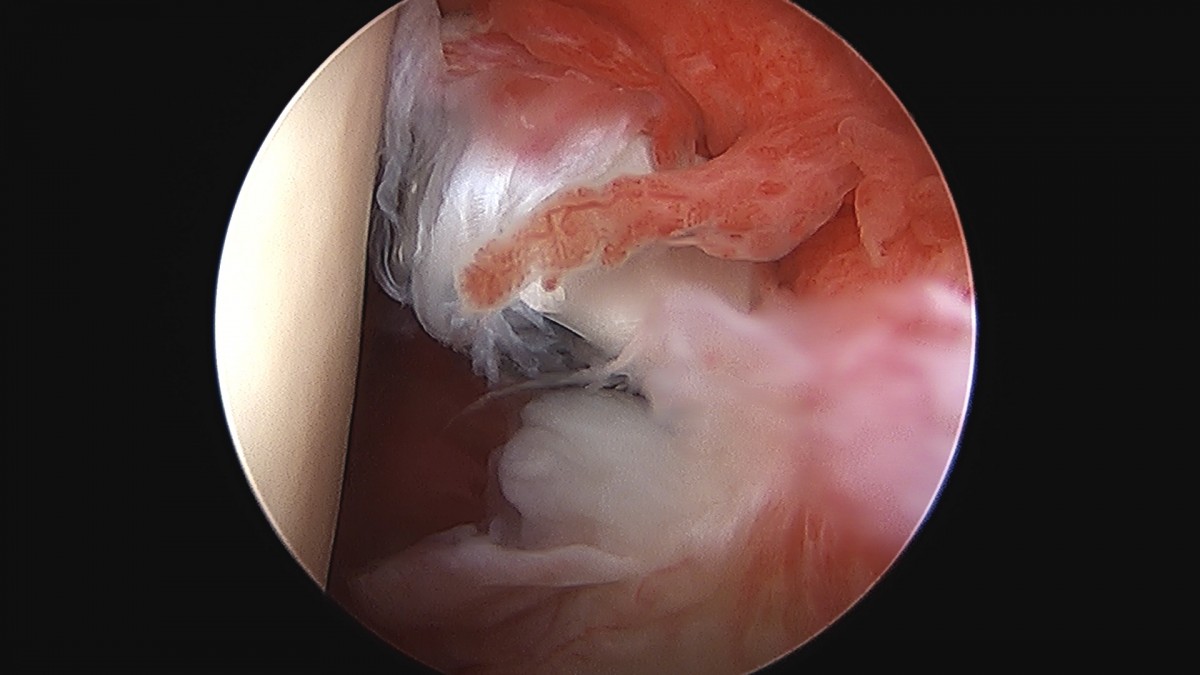

이재상원장님 어깨 견봉하 감압술 김봉O 환자

작성자 최고관리자 댓글 0건 조회 811회 작성일 25-09-16 15:28